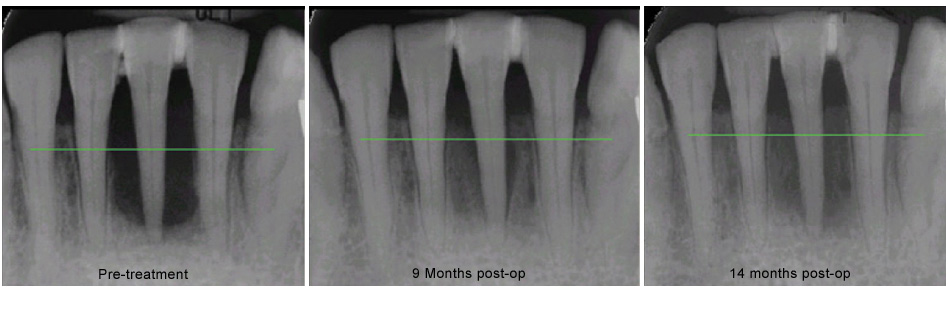

Traditional gum surgery involves cutting away some of the gum tissue, and reshaping the bone underneath. LANAP is a progressive technique using a specialized laser to destroy the bacteria that cause the disease, and alter the tissue so that it has the opportunity to heal. The use of the laser is less invasive than traditional scalpel surgery, and results in a much faster and less painful recovery.

As the gums heal, the teeth will shift, and your bite will need to be adjusted several times over the first few weeks, even for the first year and beyond. Although it seems counter-intuitive, inadequate adjustment is what is usually responsible for soreness or sensitivity following LANAP.

Professional cleaning is recommended every three months for the first year, and re-evaluation of your condition will be done at the twelve month visit. Most people with gum disease remain at risk for the rest of their lives, and would benefit from having their teeth cleaned every three months indefinitely.